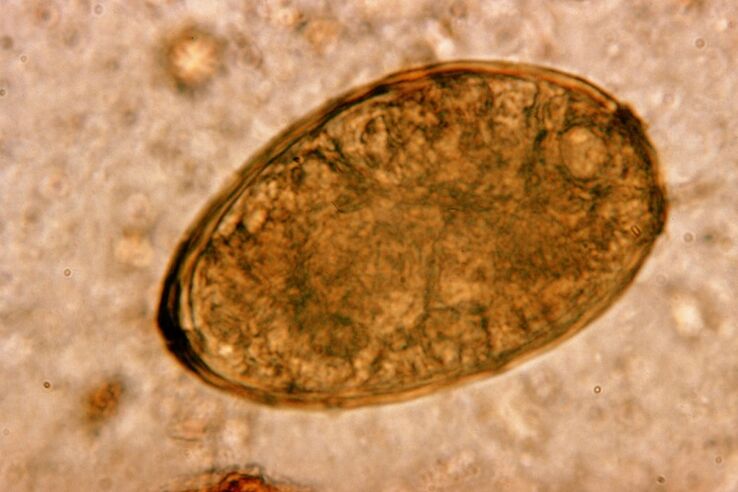

تعيش الديدان المستديرة، وهي ديدان معوية، وتتكاثر في الأمعاء. وتحدث العدوى بها عن طريق البيض الذي يدخل الجسم مع الطعام أو عن طريق الأيدي والأشياء التي يستخدمها الشخص المصاب. التربة والفواكه والخضروات واللحوم والأسماك غير المطبوخة جيدًا - كل هذا يمكن أن يدخل بيض الديدان الطفيلية إلى جسم الإنسان.

الأمر يستحق المعرفة! تسبب الديدان المستديرة السعال الجاف. تهاجر عبر الدورة الدموية، وتدخل يرقاتها إلى أعضاء الجهاز التنفسي (القصبات الهوائية والقصبة الهوائية والرئتين)، وتهيج المستقبلات وتسبب هذه الأعراض. تتراوح فترة هجرة اليرقات في جميع أنحاء الجسم من أسبوع إلى أسبوعين.

داء الاسكارس

تنتشر الديدان الخيطية على نطاق واسع، لذا فإن السعال على خلفية داء الصفر هو ظاهرة نموذجية. تحدث عدوى الدودة المعوية من خلال الطرق التقليدية لداء الديدان الطفيلية. وتشمل هذه ملامسة الأرض، وتناول الفواكه والخضروات غير المغسولة، والأيدي المتسخة.

تسبب يرقات الإسكارس المشكلة من خلال التأثير الميكانيكي على أنسجة الجهاز التنفسي. يحدث هذا خلال مرحلة هجرة الطفيلي. آلية وتسلسل تأثير الديدان الخيطية على الجهاز التنفسي للإنسان هي كما يلي.

بمجرد وصول بيض الدودة الدبوسية إلى الجهاز الهضمي، تحت تأثير الإنزيمات الخاصة بها والعصارة الهضمية، تتخلص من قشرتها وتتحول إلى يرقات. يتمتع الأخير بالقدرة على اختراق جدار الأمعاء إلى مجرى الدم. وبعد ذلك يتم نقلها عن طريق الدم إلى جميع أنحاء الجسم، وصولاً إلى الكبد والقلب والرئتين والجهاز التنفسي.

يوجد على الغشاء المخاطي للقصبة الهوائية أهداب تنقل اليرقة إلى الأعلى بحركاتها المنعكسة. في هذه الحالة، يتم تهيج المستقبلات ويحدث السعال، مما يرمي الديدان الطفيلية في الفم، حيث يتم بصقها أو ابتلاعها وتعود إلى الأمعاء.

لعِلمِكَ! عادة ما يكون السعال المصاحب لداء الصفر ظاهرة قصيرة الأمد. ولكن إذا تكررت الإصابة، فقد تصبح دائمة تقريبًا.